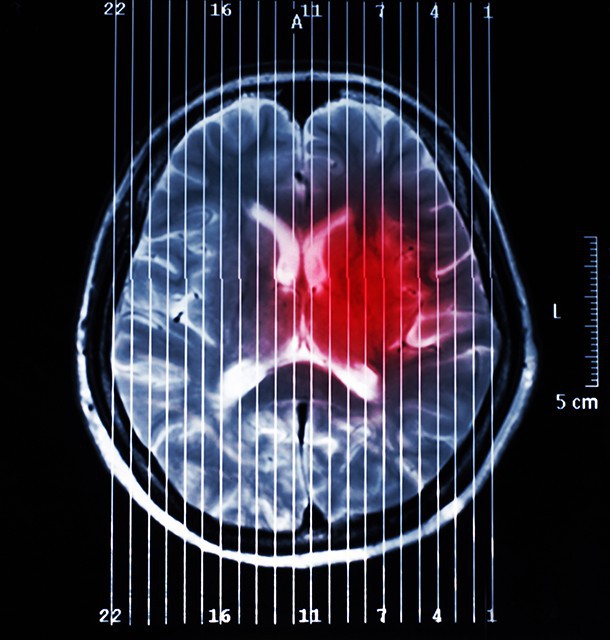

周一在《自然通訊》期刊發表的一項研究中,有研究人員找來了一共34名自願參與的成年人,分成兩組,一組有自殺念頭,另一組則沒有,並在他們思考「邪惡」或「讚美」等30個有正面、負面意思或與死亡相關的詞語的時候,進行腦部掃描觀察他們的大腦活動。

當我們想起某種東西時,我們的神經元就會以某種特定的方式發起。這樣的測量模式比其他僅研究被激活的大腦區域的腦研究更準確。研究人員發現兩組人士對以下六組字詞的反應有最大分別:死亡、煩惱、暢快、好、讚美和殘酷。

然後,研究人員將收集回來的數據輸入一個電腦程式,發現程式預測誰人有自殺意念的準確度達91%,而預測誰人以往嘗試過自殺的準確率則達94%。